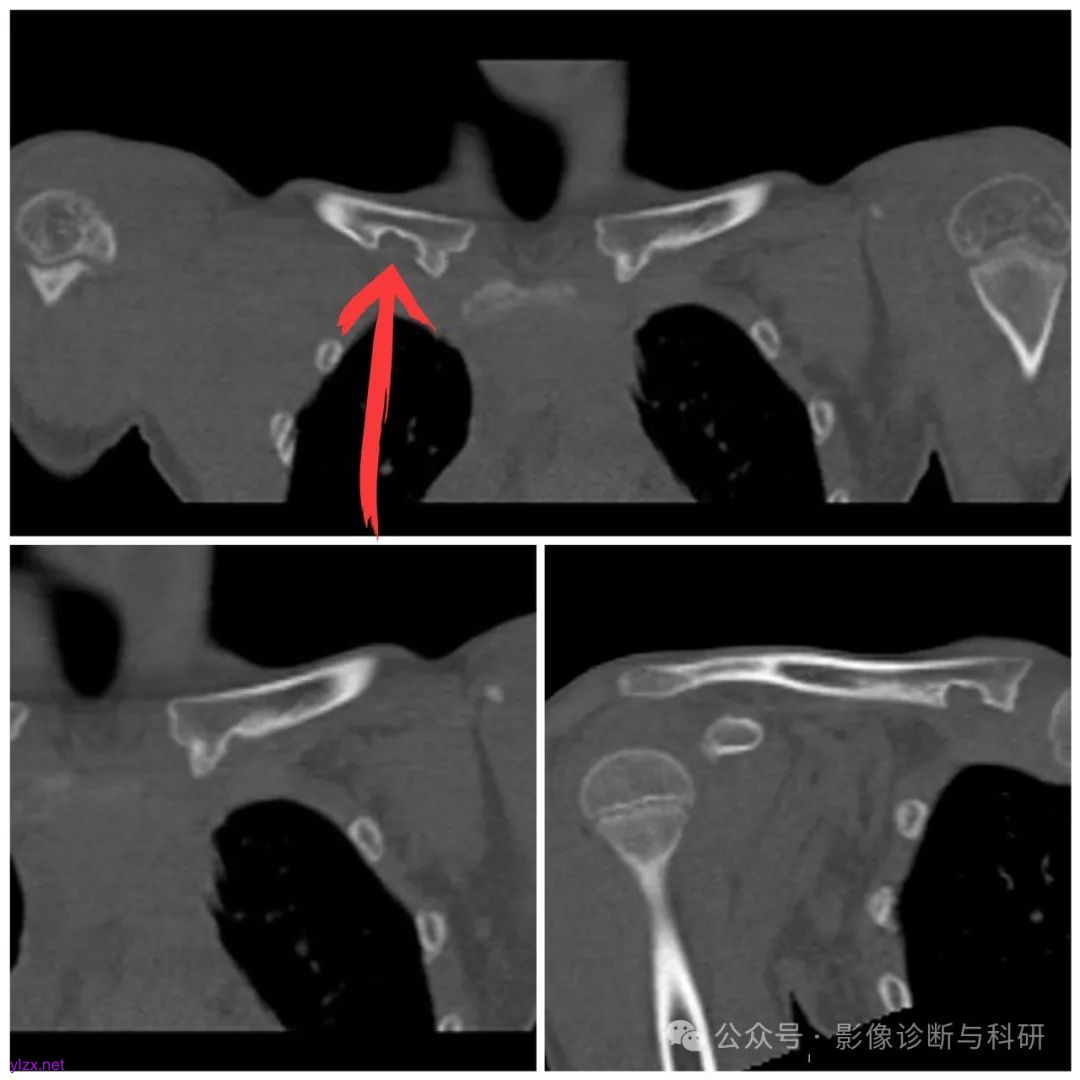

综合凹陷型锁骨菱形窝 CT 特征:

( 1 )发生于特定部位(锁骨内侧端关节面与病灶内侧缘最近点距离 2 cm 内的后下缘)的骨质缺损区。

( 2 )骨质缺损区形态呈“鱼钩征”或小圆形。

( 3 )骨质缺损区边缘硬化。

( 4 )缺损区内出现条状软组织灶(连接第 1 前肋与锁骨)。

以上特点是凹陷型锁骨菱形窝诊断依据,并且是鉴别其他病变的要点。

患者,男, 24 岁,锁骨棱形窝 1a. 横断位骨窗示左侧锁骨内侧可见类椭圆形骨质缺损区,锁骨内侧端关节面与病灶内侧缘最近点距离1.2 cm ,缺损区较大,边缘可见硬化,内侧端形态呈鱼钩样(箭头所示) 1b. 横断位软组织窗可见小条状软组织灶伸入(箭头所示) 1c. 冠状位骨窗示锁骨内侧端下缘骨质缺损,边缘硬化(来源于中国骨伤杂志)

患者,男, 48 岁,锁骨棱形窝 2a , 2b , 2c. 右侧锁骨内侧端可见小圆形骨质缺损,边缘硬化,内侧端形态呈鱼钩样(箭头所示);横断位及冠状位软组织窗可见小条状软组织灶伸入(箭头所示) 2d , 2e , 2f. 分别为 T1WI 、 T2WI 、 T2WI 压脂图像:右侧锁骨内侧端可见小圆形骨质缺损,长T1 短 T2 信号, T2 压脂可见低信号边缘可见小点状高信号灶(来源于中国骨伤杂志)